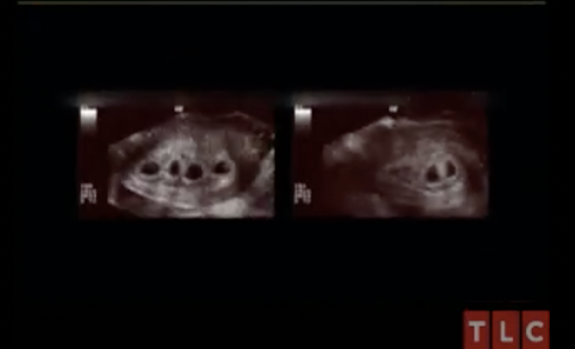

“ … So we had our first ultrasound at six weeks and there were seven babies [at the time],” Kate said. “I think they had us come back the next week– it was either the next week or two weeks, I can’t honestly remember– to see how they had progressed. In between that time, the seventh baby stopped growing.”

“I was just trying to see that ultrasound so bad and [the tech] was sort of shielding us from seeing,” Kate said. “At some point, she just got really quiet and I thought, ‘Here we go, it’s done,’ and I was really, really scared. All of a sudden, she said, ‘I see six,’ and I said, ‘You see six what?!’ and she said, ‘I see six heartbeats, they’re there.’”